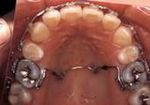

→空隙歯列 (すきっ歯)→叢生

(でこぼこ、八重歯)

子供の矯正治療(第一期治療)

主に取り外し可能な装置を用いて、生え始めた永久歯が適切な位置に生えるように促します。あごの成長の観察やコントロールもあわせて行います。治療期間は永久歯に生え変わるまでで、あごの大きさや、歯の大きさ、位置に問題がある場合は大人の矯正治療(第二期治療)へ移行します。

永久歯の矯正治療(12歳以降から)

マルチブラケット装置による治療です。(一本ごとの歯にブラケットを装着し、ワイヤーを通して歯並びを治します。)

治療期間は、個人差もありますが1年半~3年が目安です。その後、ワイヤーで治した歯並びを維持するための保定装置での観察を2年ほど行います。